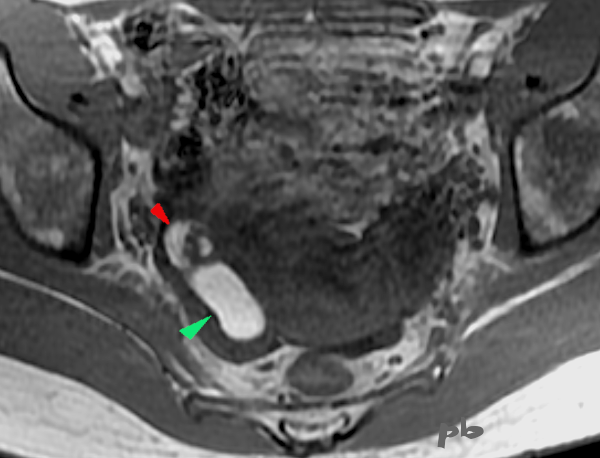

19+20+21- Kystes endométriosique et dermoïde – IRM

Sémiologie IRM comparative entre un kyste endométriosique (►) et un kyste dermoïde (►), tous les 2 ovariens droits. Ovaire gauche porteur d’un follicule dominant (★).

| T2 (image 19) | T1 sans fatsat (image 20) | T1 avec fatsat (image 21) | |

| Endométriome (►) | hypersignal | hypersignal | hypersignal |

| kyste dermoïde (►) | Hypersignal Nodule central hyposignal | Hypersignal Nodule central hyposignal | Hyposignal Nodule central hyposignal |

Le kyste dermoïde contenant de la graisse, il apparait en noir, sur la séquence T1 fatsat (qui supprime le signal de la graisse). Alors que le signal du sang ne se modifie pas. Les autres tissus contenant de la graisse ((sous-cutanés par exemple) deviennent également noirs.

L’hypersignal en T2 du kyste endométriosique n’est pas très fréquent, ni caractéristique, au contraire du »shading ». L’hypersignal en T1 fatsat permet le diagnostic.

19- T2

20- T1 sans fatsat